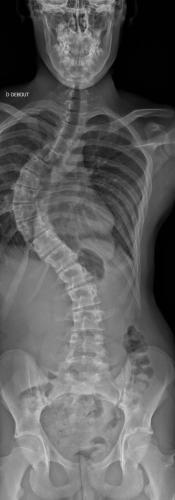

Images de scolioses opérées 16 janvier 202418 janvier 2023 par Damien Scoliose Thoracique 3 Scoliose thoracique D - Cliché pré-opératoire de Face Scoliose thoracique D - Cliché pré-opératoire de Profil Scoliose thoracique D - Cliché post-opératoire de Face Scoliose thoracique D - Cliché post-opératoire de Profil Aspect de la cicatrice à distance de l'intervention